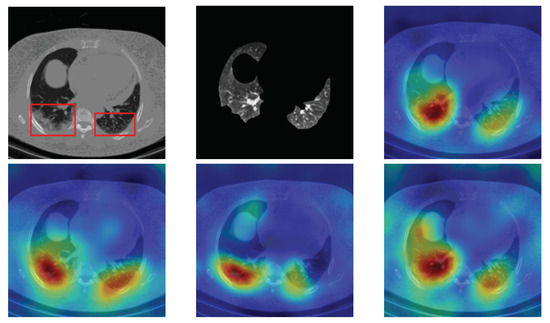

4.5. Heat Map

To have more intuition about the most important lung regions that the CNN architectures consider to classify the slice images, we used the randomized input sampling for explanations (RISE) approach [37]. Figure 13, Figure 14 and Figure 15 consist of two heat map examples of COVID-19, Cap, and normal cases, respectively. In the first example from Figure 13, we notice that despite the lung segmentation being not fully correct (it misses a considerable part of the infected region), the four CNN architectures gave more importance to the infected regions and to the lung regions in general. In the second example from Figure 13, we observe that the lung lobes were precisely segmented, and the heat maps of the four CNN architectures were well defined the infected regions, especially the Wide-Resnet-50 architecture. From both Cap examples in Figure 14, we notice that despite the lung segmentation missing considerable infected parts as well as the lung lobe regions, the heat maps of all CNN architectures give more importance to the infected region and to the lung lobes in general. This proves that the trained CNN architecture is able to define the regions of interest even when the lung lobes segmentation is not good. For the normal slice examples in Figure 15, the trained CNN architectures gave more importance to the lung lobes, especially the lower region, since the infection usually occurs there. The heat maps of COVID-19, Cap, and normal cases prove that the CNN architectures learned precisely where to look to identify the infection from the slice images.

Figure 13.

RISE heat map examples of COVID-19 slice images using the trained multi-tasks CNN architectures (ResneXt-50, Densenet-161, Inception-v3, and Wide-Resnet-50). The first example is shown in the first two rows, where the images represent the input slice image and segmented lung lobes results, followed by the heat maps of ResneXt-50, Densenet-161, Inception-v3, and Wide-Resnet-50, respectively. The second example is in rows 3 and 4.